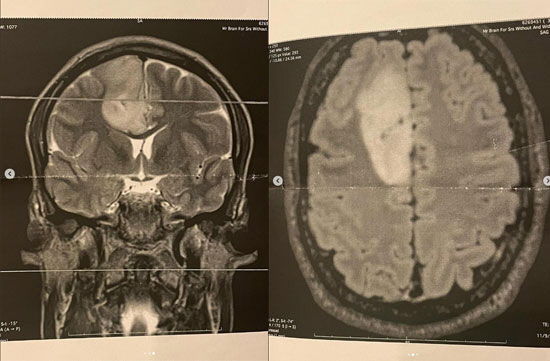

[스포츠조선닷컴 이지현 기자] 넷플릭스 스타 배우 바튼 카우퍼스웨이트(Barton Cowperthwaite)가 뇌종양 진단을 받았다.

신경교종은 뇌 또는 척수를 구성하는 세포에서 발생하는 종양으로 절반 이상이 악성으로 재발 우려가 높은 것으로 알려졌다.